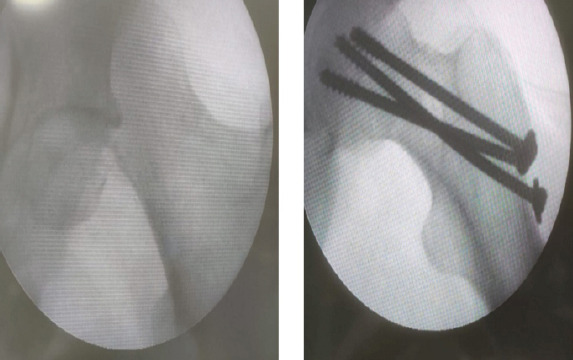

Case report: A 39-year-old male came to casualty with an alleged history of road traffic accident with multiple fractures in bilateral upper limb, multiple rib fractures, and brachial plexus injury. Computed tomography of the pelvis with both hips was done, which showed a fracture of the left femoral head with a proximal fracture fragment found inside the acetabulum with posterior dislocation of the distal part - left femoral head fracture dislocation (Pipkin type I). Closed reduction of the hip joint failed; hence, open reduction using the Kocher-Langenbeck (KL) approach was carried out, head reduced, transfixed with guide wires, and fixed with three CC screws. On the last follow-up at the end of 1 year, the patient has regained full range of motion of the hip. Patient is able to squat, sit cross-legged, and is able to walk unaided.